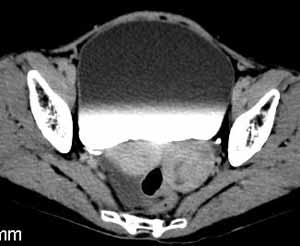

卵泡膜